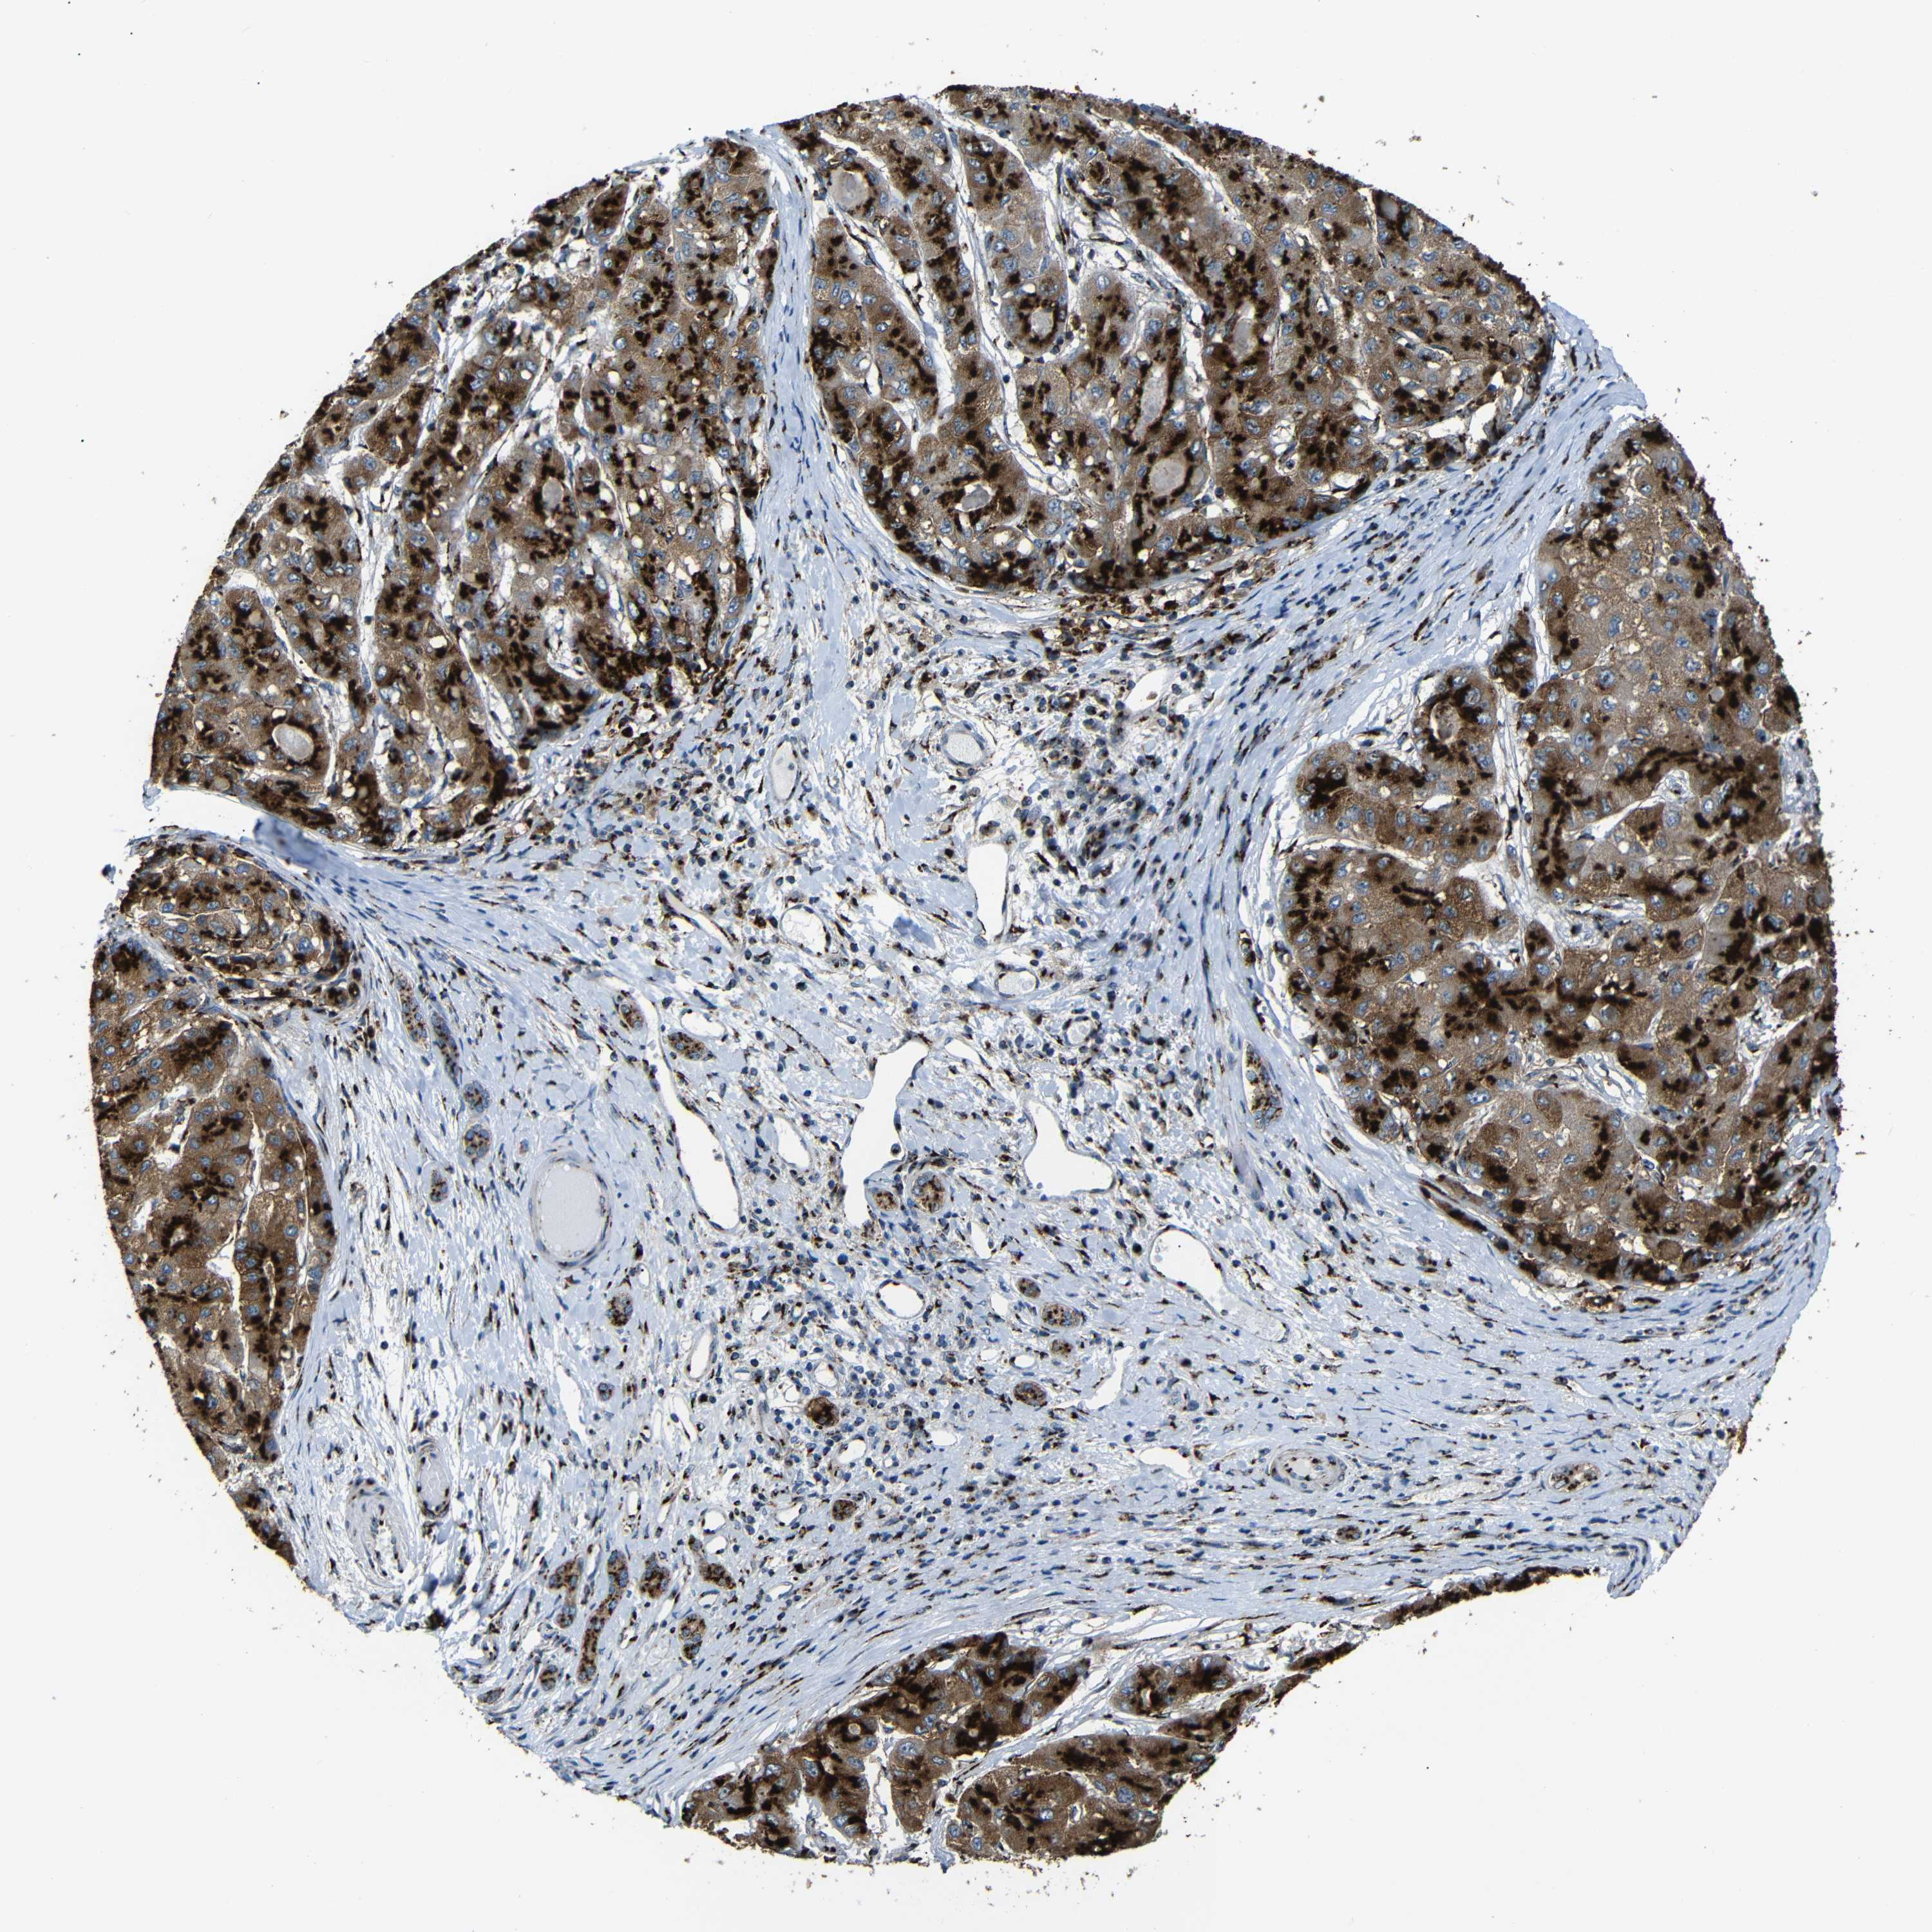

LIVER CANCER - Protein expressioni

A mouse-over function shows sample information and annotation data. Click on an image to view it in a full screen mode. Samples can be filtered based on level of antibody staining by selecting one or several of the following categories: high, medium, low and not detected. The assay and annotation is described here.

Note that samples used for immunohistochemistry by the Human Protein Atlas do not correspond to samples in the TCGA dataset.

Antibody stainingi

Antibody staining in the annotated cell types in the current human tissue is reported as not detected, low, medium, or high, based on conventional immunohistochemistry profiling in selected tissues. This score is based on the combination of the staining intensity and fraction of stained cells.

Each image is clickable and will lead to virtual microscopy that enables deeper exploration of all samples and also displays staining intensity scores, fraction scores and subcellular localization as well as patient and tissue information for each sample.

Antibody HPA012609

Antibody HPA012723

Antibody CAB011489

Staining

High

Medium

Low

Not detected

Intensity

Strong

Moderate

Weak

Negative

Quantity

>75%

75%-25%

<25%

None

Location

Nuclear

Cytoplasmic/membranous

Cytoplasmic/membranous,nuclear

Cholangiocarcinoma

Carcinoma, Hepatocellular, NOS